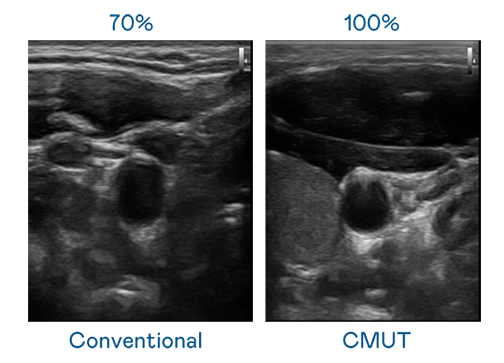

CMUT 技术是一种用电容式微机电元件来产生超音波讯号的技术。与传统 PZT 压电式技术相比,CMUT 频宽增加 30%,更宽频的超音波讯号让影像解析度大幅提升,是实现高影像品质医疗超音波扫描、促进精准医疗发展的关键技术。

大频宽带来超清晰影像

超音波影像的解析度高低,首先取决于探头能发出的讯号频宽。天美mv麻花星空mv天频在线看 CMUT 可提供高清晰的超音波讯号,提供高频宽、高灵敏度、影像纹理细节更高的超音波影像,协助医护人员缩短影像判读时间及利用精准的医疗影像进行诊断。